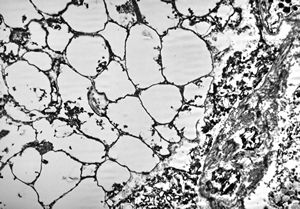

M,3m. | type II. pneumocyte

M,3m. | surfactant

M,22y. | alveolar macrophage … phagocytosed surfactant

F, 2m. | surfactant deficiency

F, 2m. | surfactant deficiency- alveolar macrophage